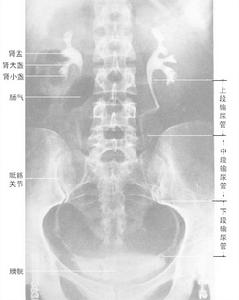

靜脈腎盂造影止痛藥腎病的腎臟表現是非特異性的,在仔細詢問病史的同時如臨床上出現腎病綜合徵急性腎功能衰竭、慢性腎功能衰竭以及高血壓、貧血腰痛或血尿尿液分析正常或有無菌性膿尿、血尿蛋白尿,(臨床表現可為輕度蛋白尿,也可為腎病綜合徵範圍蛋白尿可超過3.5g/d);CT掃描或靜脈腎盂造影可見患者出現部分和全部的腎乳頭壞死腎臟縮小腎盞變鈍等與慢性腎盂腎炎相似的改變,既可考慮本病診斷

2、放射學檢查主要是用靜脈腎盂造影和CT掃描來診斷或排除止痛藥腎病,25%~40%的患者可以出現部分和全部的腎乳頭壞死;其餘的大多數患者則表現為腎臟縮小腎盞變鈍、與慢性腎盂腎炎相似靜脈腎盂造影對缺血性腎病診斷有一定的限制性(敏感性低並對腎功能受損的患者有潛在的腎毒性)。